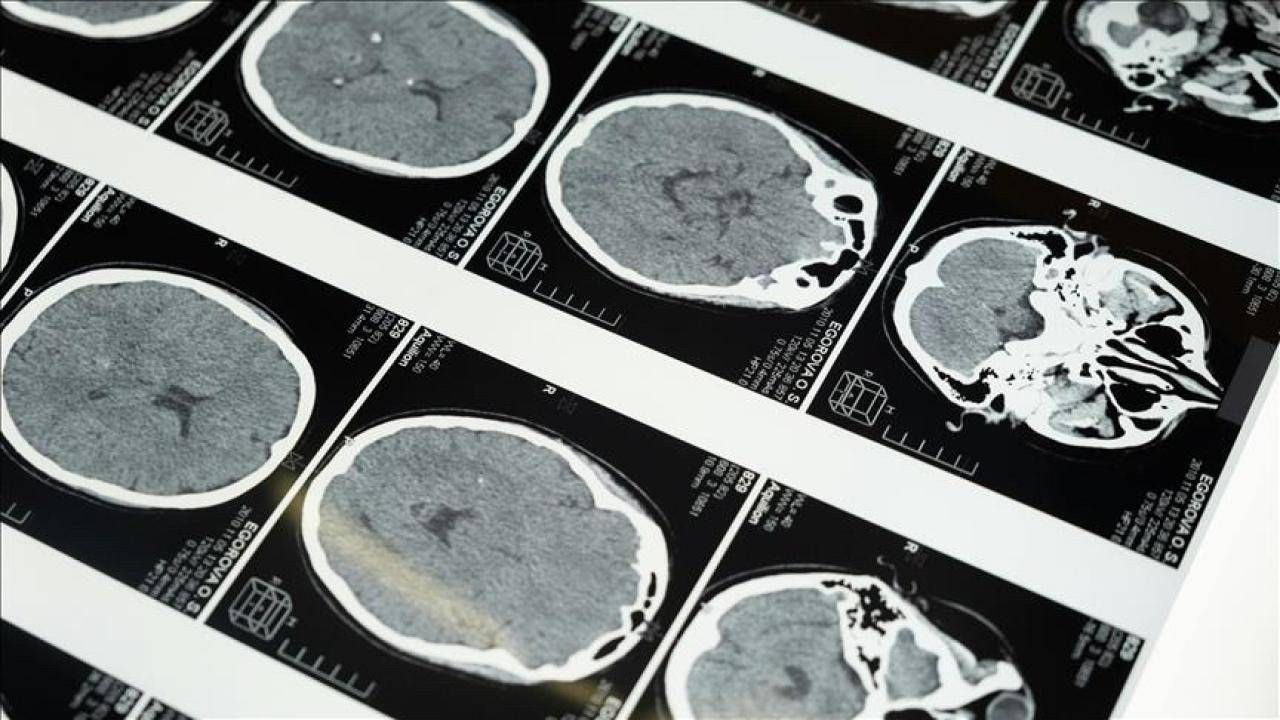

İstanbul'da düzenlenen 1. Dünya Girişimsel Nöroloji ve Nöroşirürji Kongresi'nin (WINNC 2025) düzenleme komitesinde yer alan Eskişehir Osmangazi Üniversitesi Tıp Fakültesi Nöroloji Ana Bilim Dalı Öğretim Üyesi ve İnme Merkezi Sorumlusu Prof. Dr. Atilla Özcan Özdemir, inmenin beyin damarlarının tıkanması (iskemik) ve beyin kanaması şeklinde gelişen iki türünün olduğunu söyledi.

"Özellikle pıhtıyla tıkanan beyin damarının açılmasıyla ilgili stratejiler gelişti. İnmede erken dönemde yapılan damar açma tedavileri konusunda ülke olarak iyi durumdayız. İnme tedavisinde pıhtıyla tıkalı beyin damarının anjiyo yoluyla açılması mümkün. Böylelikle hastanın 3 ay sonra, 1 yıl sonra kendi işini yapabilecek hale getirilmesi sağlanabiliyor. İnme merkezlerinde uygulanabilen bu işlemi ilk 24 saat içerisinde belirli hasta gruplarına yapabiliyoruz. İlk 24 saat çok kritik, bu müdahaleler de sadece inme merkezlerinde yapılabiliyor."